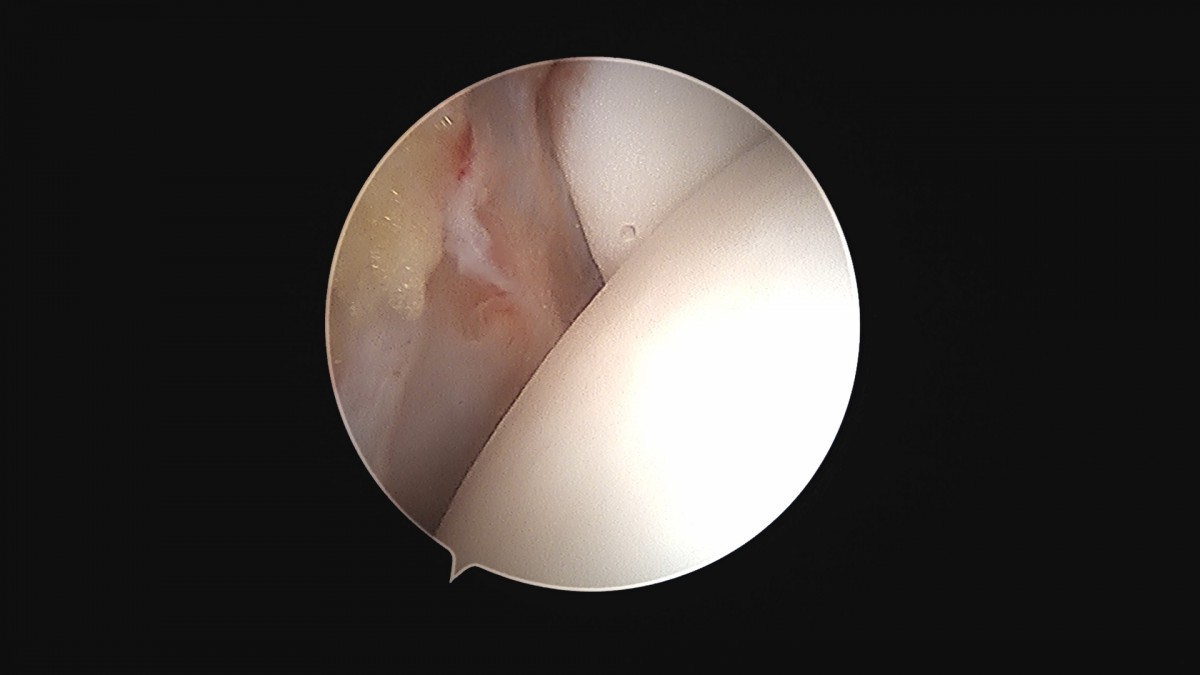

이재상원장님 발목 활액막 절제술 및 인대 봉합술 신진O 환자

작성자 최고관리자 댓글 0건 조회 790회 작성일 25-09-16 15:22